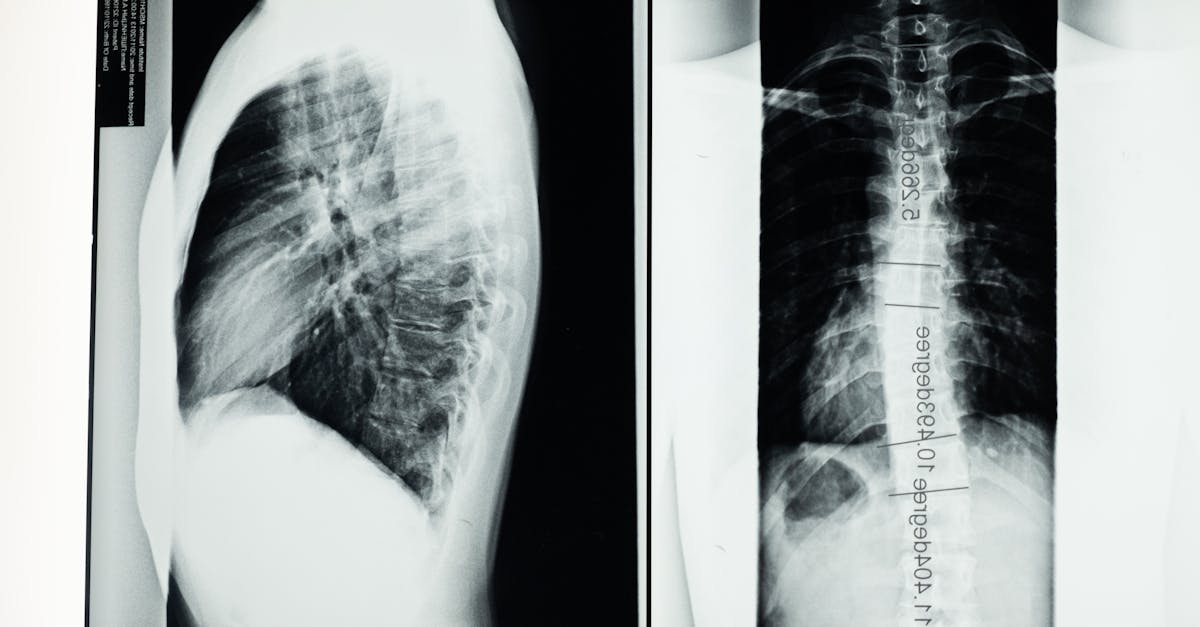

Lumbar spinal stenosis and degenerative spondylolisthesis are prevalent spinal conditions affecting many patients who experience pain, numbness, and reduced mobility due to nerve compression. Surgical interventions aim to decompress nerves and stabilize the spine, commonly through fusion or more recently, motion-preserving implants like the TOPS System. For patients contemplating surgery, it is crucial to comprehend the differences between these approaches.

- Comprehensive initial evaluation: Patients are assessed by experts experienced in spine disorders, including an extensive review of history, imaging, and clinical findings. Utilizing evidence-based methods ensures accurate appraisal of surgical candidacy and tailored recommendations.